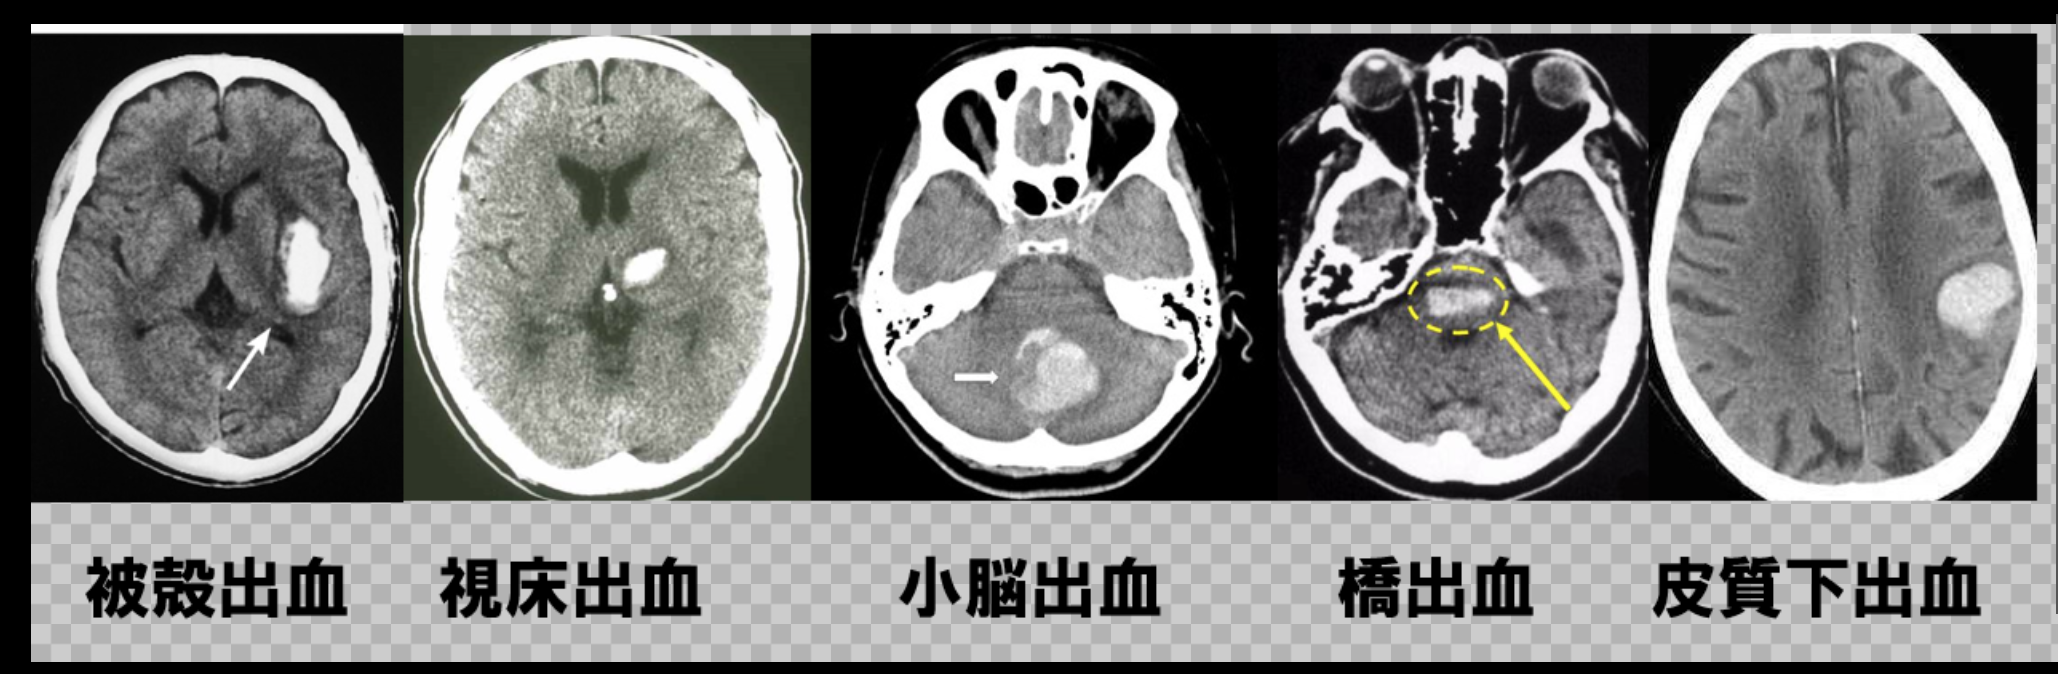

脳出血│標準医療情報センター